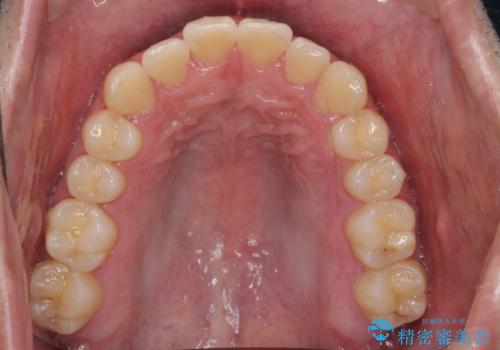

前歯のがたつき マウスピース矯正で 非抜歯で奥歯を後ろに下げる治療

- 前歯のがたつきを主訴に来院。

歯を抜かずに、奥歯を後ろに下げ、歯の両側をわずかに削って並べました。

歯のがたつきがなくなると、歯ブラシがしやすくなり、茶色いステインも付きにくくなります。